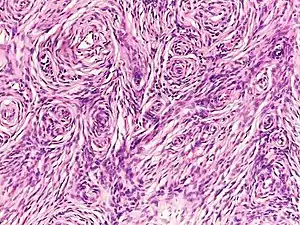

Histopathology of neurofibroma: A spindle cell lesion composed of slender fibroblast-like cells with storiform pattern and very low amount of stroma.[16]